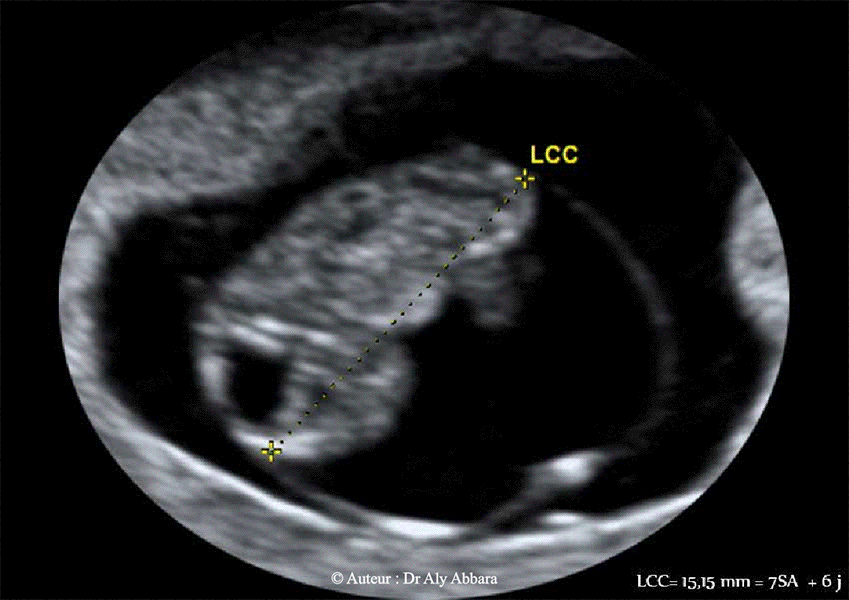

Cerveau embryonnaire - coupe échographique sagittale médiane - embryons âgé de 7 SA + 6 jours à 9 SA et 3 jours :

Analyse des éléments formant la

fosse rhombencéphalique

(ou courbure pontique) et leur futur

développement